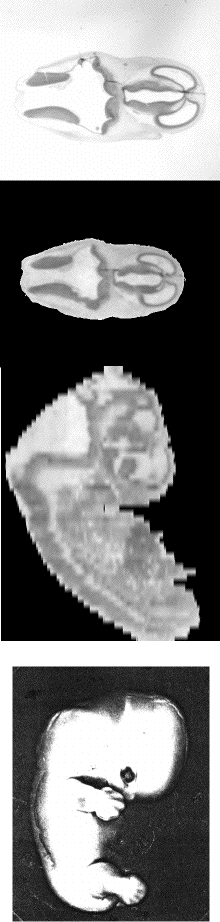

@@@In the Congenital Anomaly Research Center of Kyoto University, approximately 1000 specimens are maintained in serial sections. This fetal library is used to establish normal standards of human preneral development and to find the real incidence of anomalies. The system, Virtual Embryology, is designed to help understanding the structure of embryo using 3D image reconstructed from these microscopic serial sections. A user can "dissect" the virtual embryo on a computer display and browse it from arbitrary viewing angle. Also an animation of virtually growing embryo can be shown in this system.

3D surface view

Resected view

But on a standalone system(Mac + NIH Image), it works as this.